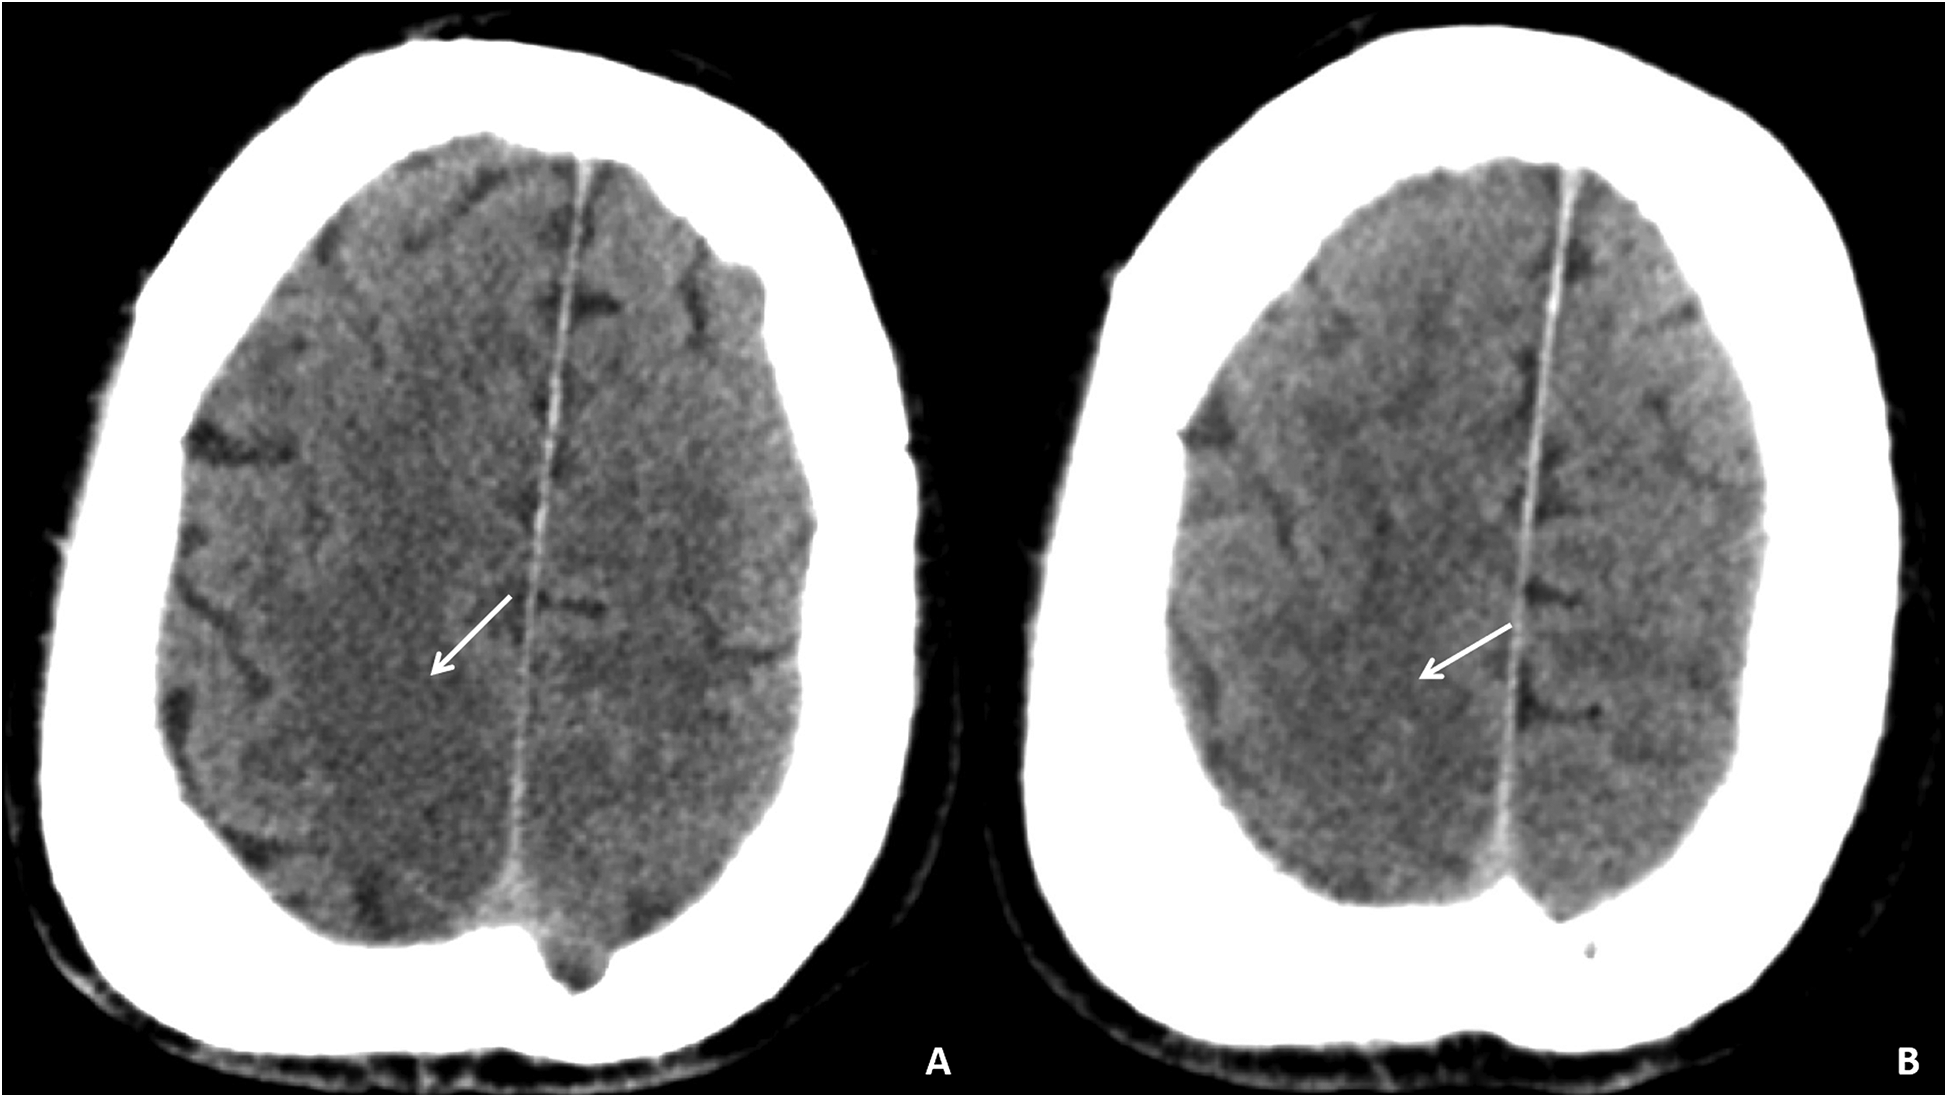

Auxiliary examinations included cerebral artery computed tomography angiography (CTA), which revealed cerebral atherosclerosis with mild local luminal stenosis. CT scans of the head and chest revealed a slightly hypoattenuating area in the right frontoparietal junction (Figure 1) and a radiolucent area in the left atrial region suggesting possible air accumulation (Figure 2). Specifically, the cranial CT images upon admission showed slightly lower density areas with unclear boundaries, primarily located in the white matter region of the right parietal lobe, indicative of an acute ischemic event rather than chronic changes. The presence of these hypodense areas, combined with the patient's clinical presentation and elevated troponin levels, suggested an acute ischemic stroke. These findings warranted further investigation. Electrocardiogram (ECG) findings indicated atrial flutter with rapid ventricular response, ST-segment elevation in the inferior leads with abnormal Q waves, and incomplete right bundle branch block (Figure 3A). The patient had a history of atrial fibrillation and had undergone RFA one month prior at another hospital. The provisional diagnoses included cerebral infarction, shock, coma, and heart failure. The patient's history included RFA for atrial fibrillation. As the patient was within the therapeutic window for stroke, treatment with 1 million IU of urokinase for thrombolysis was initiated with consent. Urokinase, a fibrinolytic agent effective in dissolving clots and restoring blood flow, was chosen for its balanced safety and efficacy, especially crucial for rapid reperfusion. Compared to alteplase (tPA), urokinase may reduce the risk of systemic bleeding complications in certain patients. Symptomatic and supportive measures, including fluid resuscitation and vasopressor support, were provided to improve cerebral circulation and for early secondary prevention of stroke. Continuous monitoring of cardiac and hemodynamic parameters was also conducted.

Figure 1

Cranial CT images of the patient upon admission. Slightly lower density areas with unclear boundaries, primarily located in the white matter region of the right parietal lobe, are visible on two different axial sections (A,B).